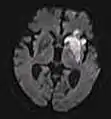

Diffusion weighted (DWI)ConventionalDWIMeasure of Brownian motion of water molecules.[26] High signal within minutes of cerebral infarction (pictured).[27]

Apparent diffusion coefficientADCReduced T2 weighting by taking multiple conventional DWI images with different DWI weighting, and the change corresponds to diffusion.[28] Low signal minutes after cerebral infarction (pictured).[29]